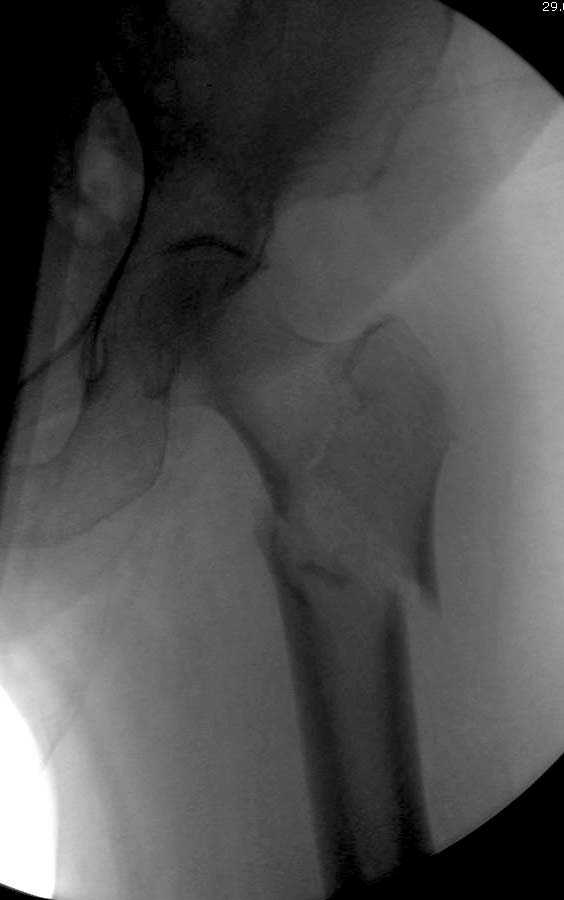

Здесь представлен случай, где в послеоперационном периоде обнаружена техническая ошибка, Gamma 3 установлен с нарушением методики. Больная в 91 лет, прооперирована через день после поступления и выписана через 48 часов.

При первом послеоперационном поликлиническом осмотре больная предъявила жалобы на боли в бедре. В серийных снимках обнаружен продольный перелом верхнего отдела бедра.

Считаем, что техническая ошибка произошла во время установки гвоздя, когда рассверливанию канала не уделили должного внимания. Канал остался узковат, и гвоздь был забит с силой. Полная нагрузка конечности приостановлена на две недели, и боли в конечности изчезли. Больная начала нагрузку и перелом срастается.-- Djoldas Kuldjanov, M.D.Associate ProfessorDepartment of Orthopedic SurgerySt. Louis University

Мне тоже представляется, что это не единственная проблема. Продольные трещины заживают легко и быстро. Интересно, почему увеличился варус и

появилась медиализация дистального отломка.